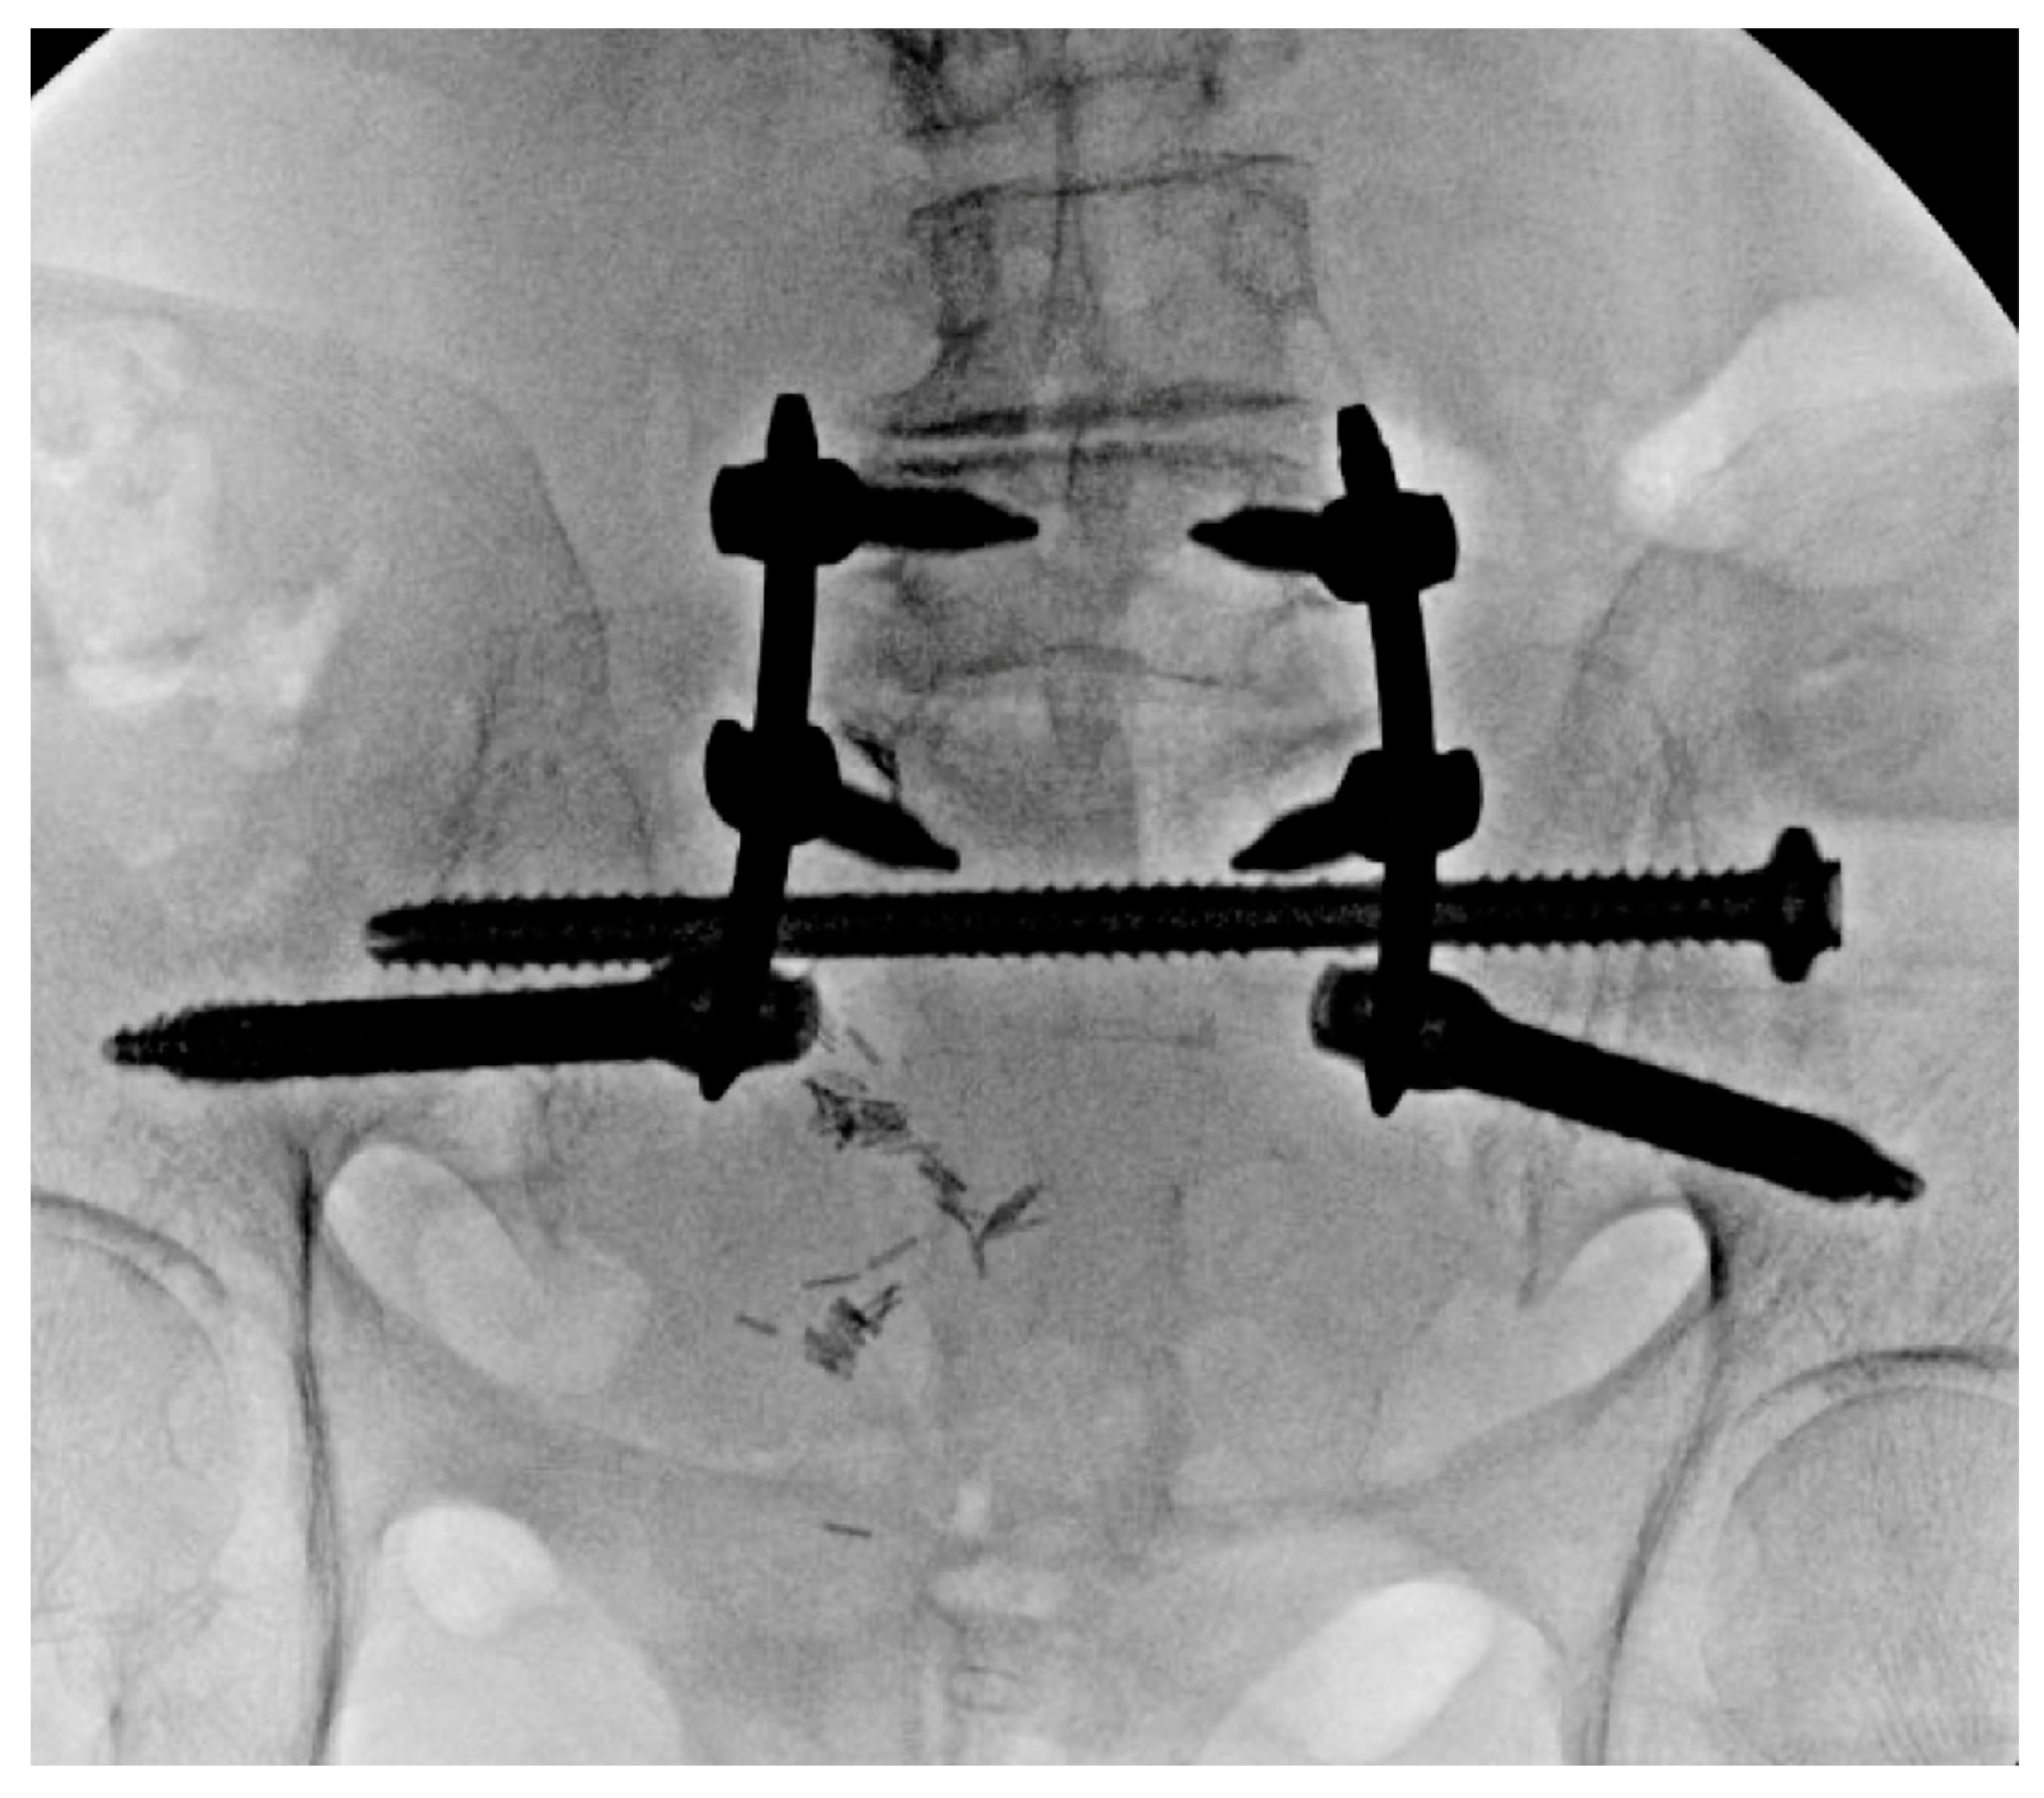

6. Spinopelvic Fixation Percutaneous Technique

7. Tran-Sacral Percutaneous Technique